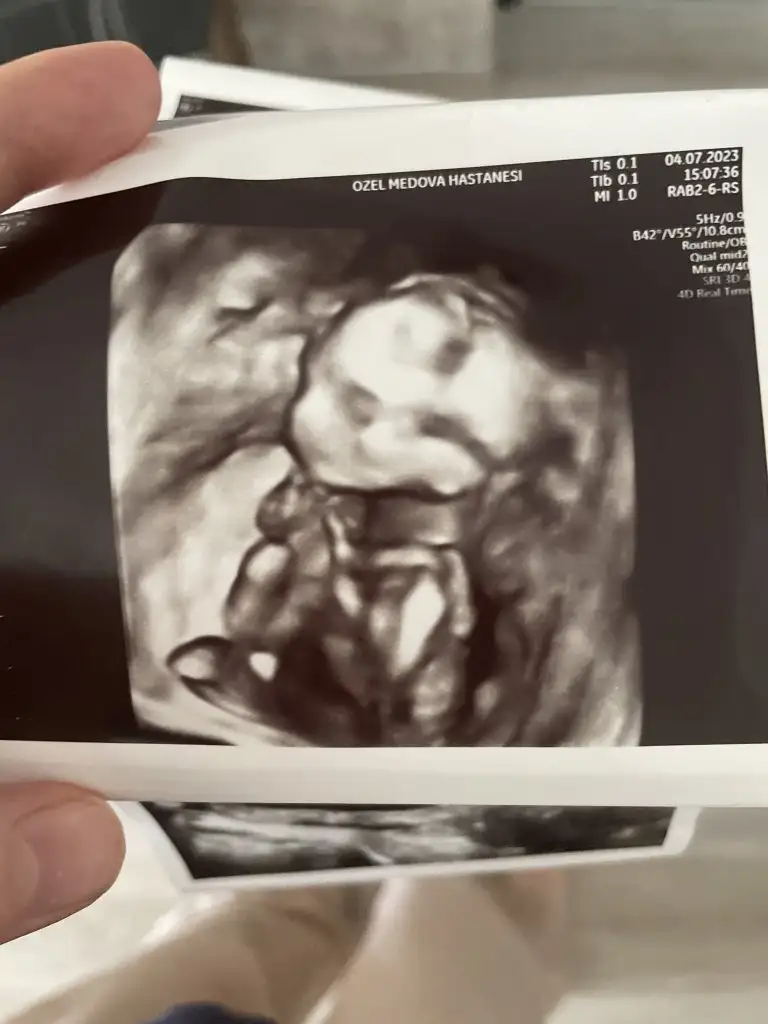

16. Haftada 10.8 cmmiş galiba ben öyle algıladım. Boyunu kilosunu falan söylemişti ama unuttumOna da baktım şimdi en son 12+2 yken yazıyor 5.58 cm miş o zaman. Son ultrason kağıtlarımda yok crl

Seninkinde yazıyor canım. Görüntü de çok iyi.Benim ultrason görüntülerini anla anlayabilirsen16. Haftada 10.8 cmmiş galiba ben öyle algıladım. Boyunu kilosunu falan söylemişti ama unuttum